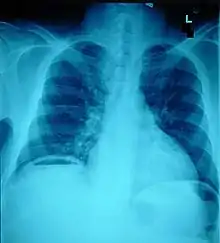

Diagnosis

Ten percent of people with polytrauma who had no signs of abdominal injury did have evidence of such injuries using radiological imaging.[1] Diagnostic techniques used include CT scanning, ultrasound,[1] and X-ray.[7] X-ray can help determine the path of a penetrating object and locate any foreign matter left in the wound, but may not be helpful in blunt trauma.[7] Diagnostic laparoscopy or exploratory laparotomy may also be performed if other diagnostic methods do not yield conclusive results.[5]